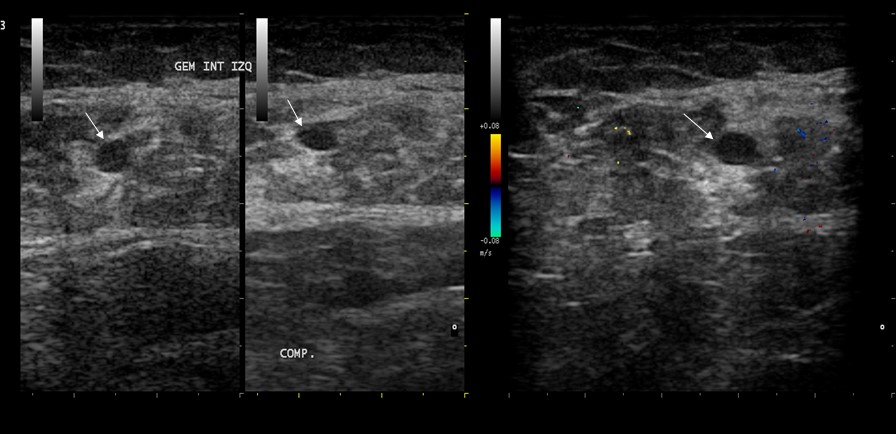

En el espesor de los músculos de los miembros inferiores existen venas musculares que drenan durante la sístole muscular (contracción muscular) hacia la vena poplítea y el tronco tibioperoneo: son los senos venosos soleos y gemelares (mediales y laterales) que, a diferencia del resto de las venas sistémicas, no presentan sistema valvular y su funcionamiento depende de la contracción muscular (bomba veno-muscular).